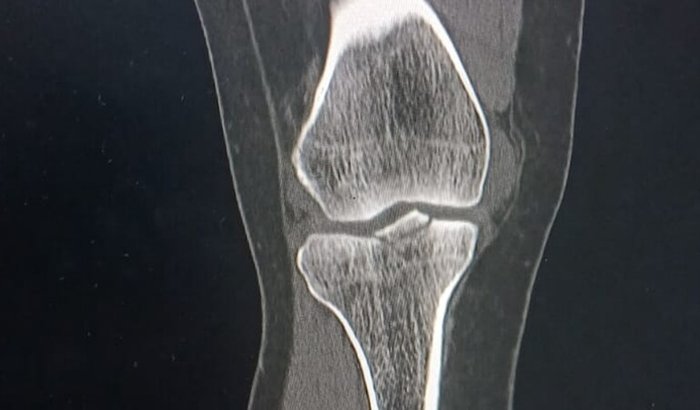

Hoje, ao levar meu filho de bicicleta elétrica para a pré-escola, sofri um acidente inesperado: uma criança correndo acabou me atropelando, e na queda fraturei o joelho.

O diagnóstico médico aponta:

➡️ Fratura do platô tibial lateral, com extensão para as eminências intercondilianas, com desnivelamento ósseo de até 2 mm

➡️ Derrame articular com extensão para a bursa supra-patelar